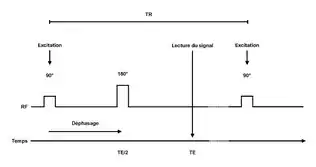

Une séquence se caractérise par deux principaux paramètres:

- Le temps d'écho (TE), durée entre le sommet de l'impulsion d'excitation et la moitié du temps de lecture,

- Le temps de répétition (TR), durée au bout de laquelle on reproduit la séquence.

La première séquence IRM employée fut la séquence écho de [1]spin. Cette dernière se décompose en:

- Une impulsion 90° dite d'excitation à t=0

- Une période de déphasage des spins dans le plan transverse des protons pendant TE/2

- Une impulsion 180°, dite d'inversion

- Un rephasage pendant TE/2

- La lecture du signal (lecture de l'écho de spin) à TE